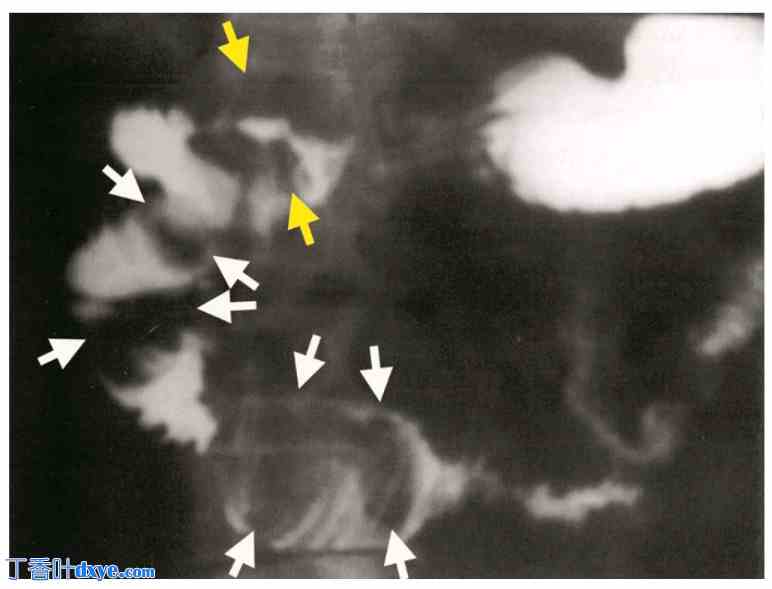

图7

胃十二指肠通道示胆囊十二指肠瘘(黄色箭头),十二指肠内有嵌顿结石。十二指肠球部可见清晰的椭圆形充盈缺损(白色箭头)。

图8

胃十二指肠通道示多个椭圆形充盈缺损,清晰地位于十二指肠球部(黄色箭头),并延伸至十二指肠D1、D2和D3-D4段(白色箭头)。